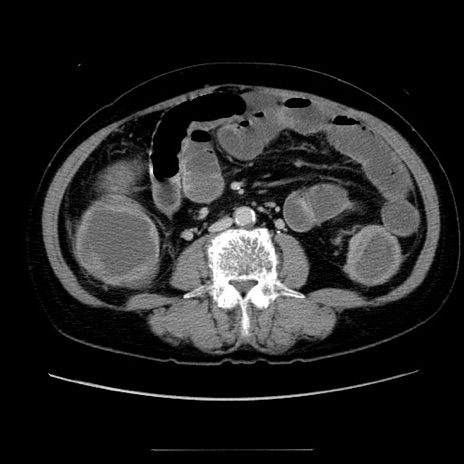

症例5(横断像)

【症例】70歳代女性

【主訴】お腹が張る

【現病歴】1週間くらい前から腹部膨満の自覚あり。昨日夜から増悪したため、本日救急外来受診。

【身体所見】意識清明、BT 36.5℃、BP 165/106mmHg、HR 80bpm、SpO2 98%、腹部:膨満、軟、自発痛・圧痛なし、触診にて不快感あり、腸蠕動音:減弱

【データ】WBC 12600、CRP 1.04